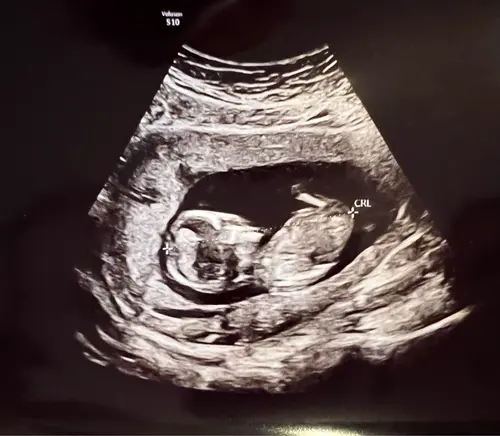

Hoi mama’s,

We hebben een hele mooie echo gehad. Alles is mooi tot in detail bekeken. Hartje perfect, hartkleppen perfect. Teentjes geteld enzo. Mooi gegroeid, veel vruchtwater, nieren oké,…. Was een dokter en een gynaecologe en die waren beiden voorzichtig positief. Alleen kunnen we pas echt gerust zijn als we woensdag de uitslag krijgen 🍀